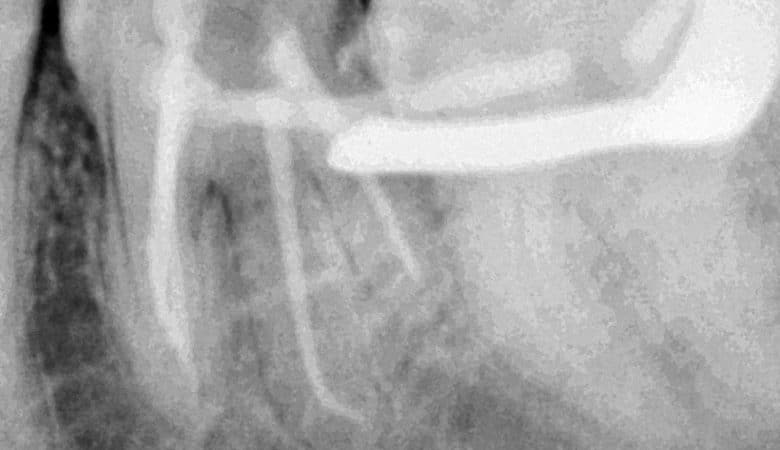

Radix entomolaris 45 years old lady came with symptomatic lower 6 which was treated previously with “pulpotec” &because of that there was an apical &coronal calcification in the mesiobuccal canal Unfortunately the last 2 ml of the canal I can’t…